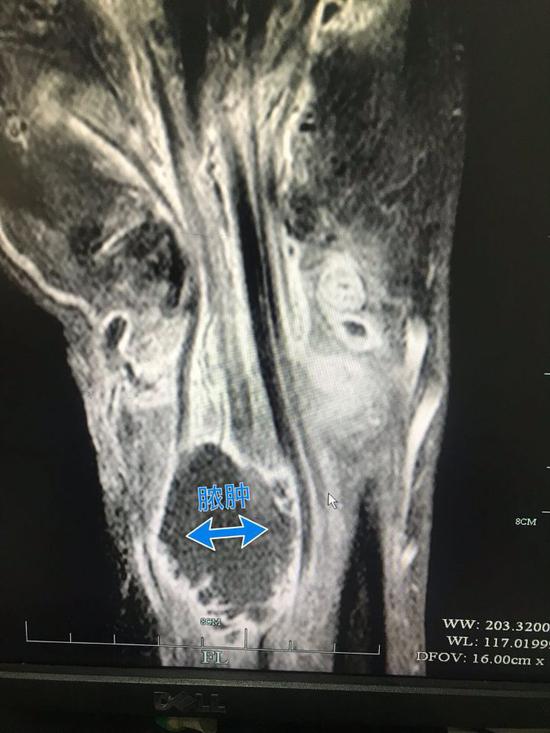

半年之后,姚先生找到了杭州的一家医院,检查显示姚先生的右手腕持续流脓,伴随着恶臭和疼痛,CT片显示脓肿肌腱断裂,医生告诉姚先生,这种情况可能要截肢。

经检查,原来真凶是杀手上线——海分枝杆菌,是一种存在于海水和淡水中的细菌,适宜生存温度为28到30摄氏度,所以入侵人体后,就会在人体的筋膜蔓延,作用于人们的手、脚等远肢端。而一旦被海产刺伤而感染了这种细菌,伤口可能并不会流血,只会不断肿胀,加上它的生长速度很慢,所以不仅姚先生1年多才发现真凶,很多人都会因为一开始忽视它而大吃苦头。